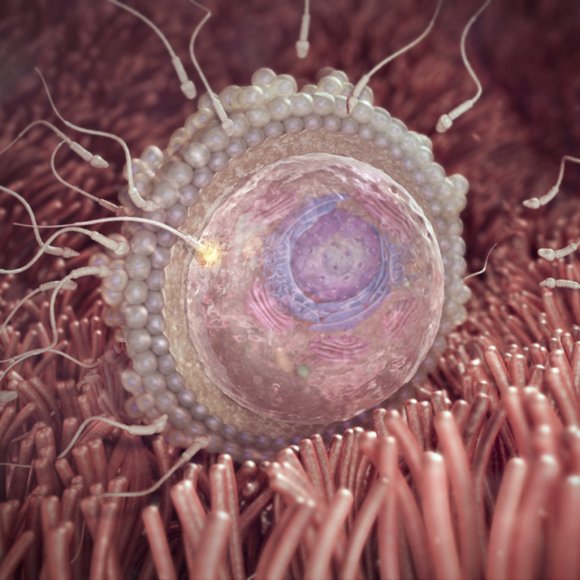

Infertility Treatment★New

(Nirmala Madilu - Test Tube Baby Center)

The use of medical techniques to improve the ability of a women or couple to conceive children....

Infertility/IVF Clinic